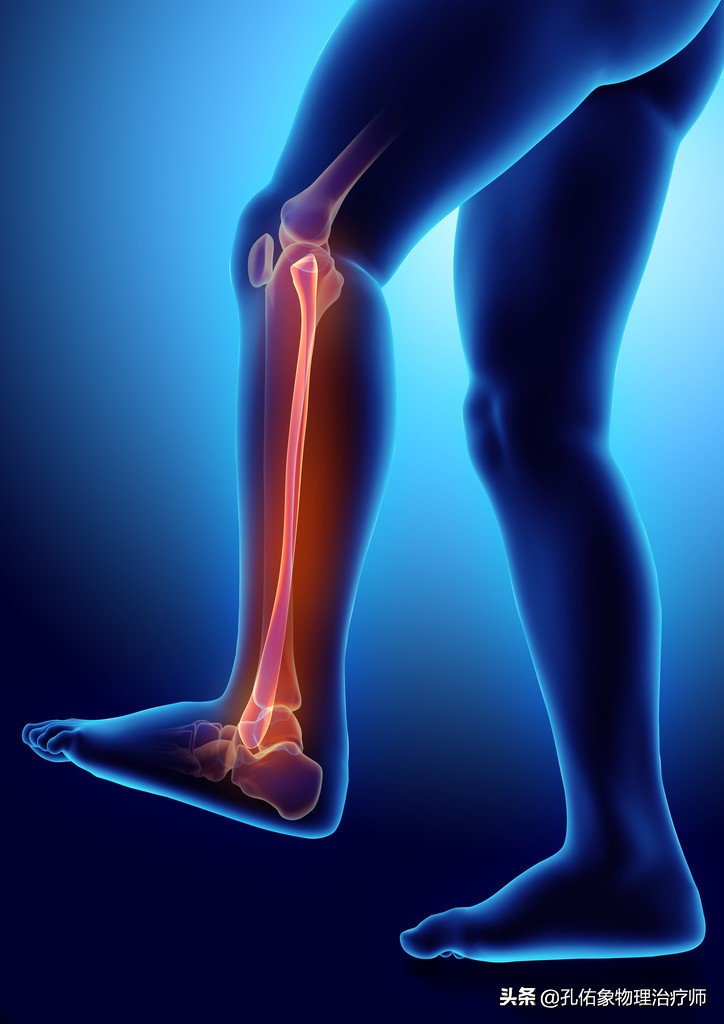

2.足底疼痛

膝关节痛骨性关节炎的治疗方法,膝骨性关节炎的手法治疗视频

当你膝盖出现疼痛,走路自然而然就会出现疼痛步态,为了躲避疼痛而行走,就会改变身体结构的力学负荷,引起脚巴掌的受力不均匀而出现踝足的肿胀疼痛;到医院去拍片检查,也会发觉什么问题也看不出来,还是正常的,就是疼痛,就是查不出具体的原因,有可能就是膝痛的导致的。

因为膝痛,会使稳定膝盖骨周围的韧带、肌肉打破原有的平衡;比方说现在很多人因不注意锻炼,常见于大腿外侧很紧,而膝盖骨内上缘处的股内侧斜肌就会很弱,从而影响到膝的受力,就会导致小腿发生旋转,最终使脚巴掌发生受力不均的情况下行走,毫无疑问就会出现足底疼痛。